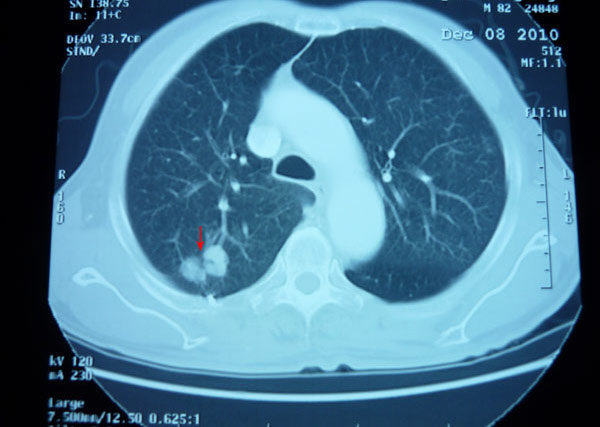

2010年 7月,廖老当时82岁,因反复咳嗽、咳痰10余年,住进南宁市一家医院,经CT检查发现右下肺有2×2×2..5cm肿块,经病理检查诊断为右肺腺癌。当时在医院进行了“粒子植入法”治疗,后又经朋友介绍于2011年底到广州一家私立医院行 “干细胞移植术”,疗效均不佳。

廖老右上肺癌治疗前